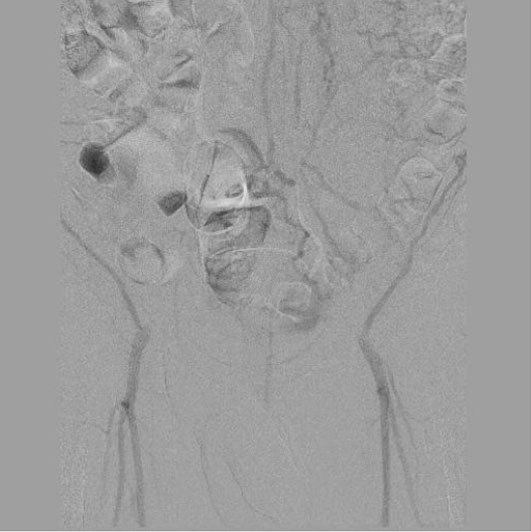

Пациенту была выполнена высокотехнологичная миниинвазивная эндоваскулярная операция – баллонная ангиопластика и стентирование брюшного отдела аорты, левой и правой подвздошных артерий, с хорошим результатом, с полным восстановлением прямого кровотока на всем протяжении обеих нижних конечностей. Данная операция миниинвазиваная, длилась 2.5 часа, была выполнена через 2 маленьких прокола в руке и ноге под местной анестезией и является альтернативой большой и долгой полостной операции, с разрезом брюшной полости под общим наркозом, которые чаще всего выполняются при таком сложном поражении.